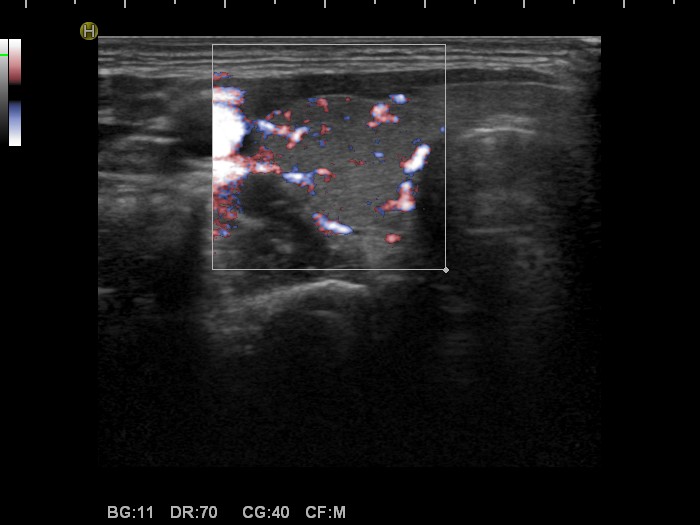

Right lobe, longitudinal scan

Right lobe, transverse view, color Doppler fine flow method. The vascularization is a little bit increased.